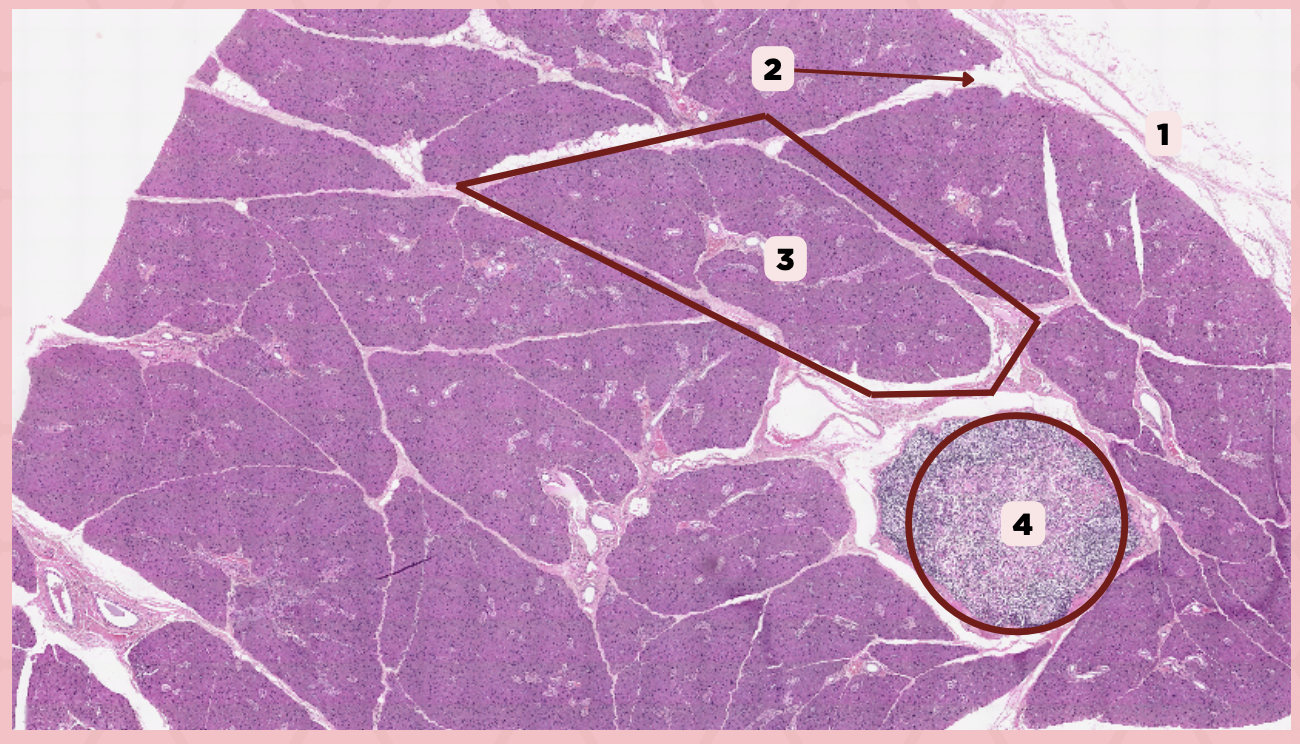

Submandibular

Identify the specimen.

Capsule

Identify the structure labeled as 1.

Septa

Identify the structure labeled as 2.